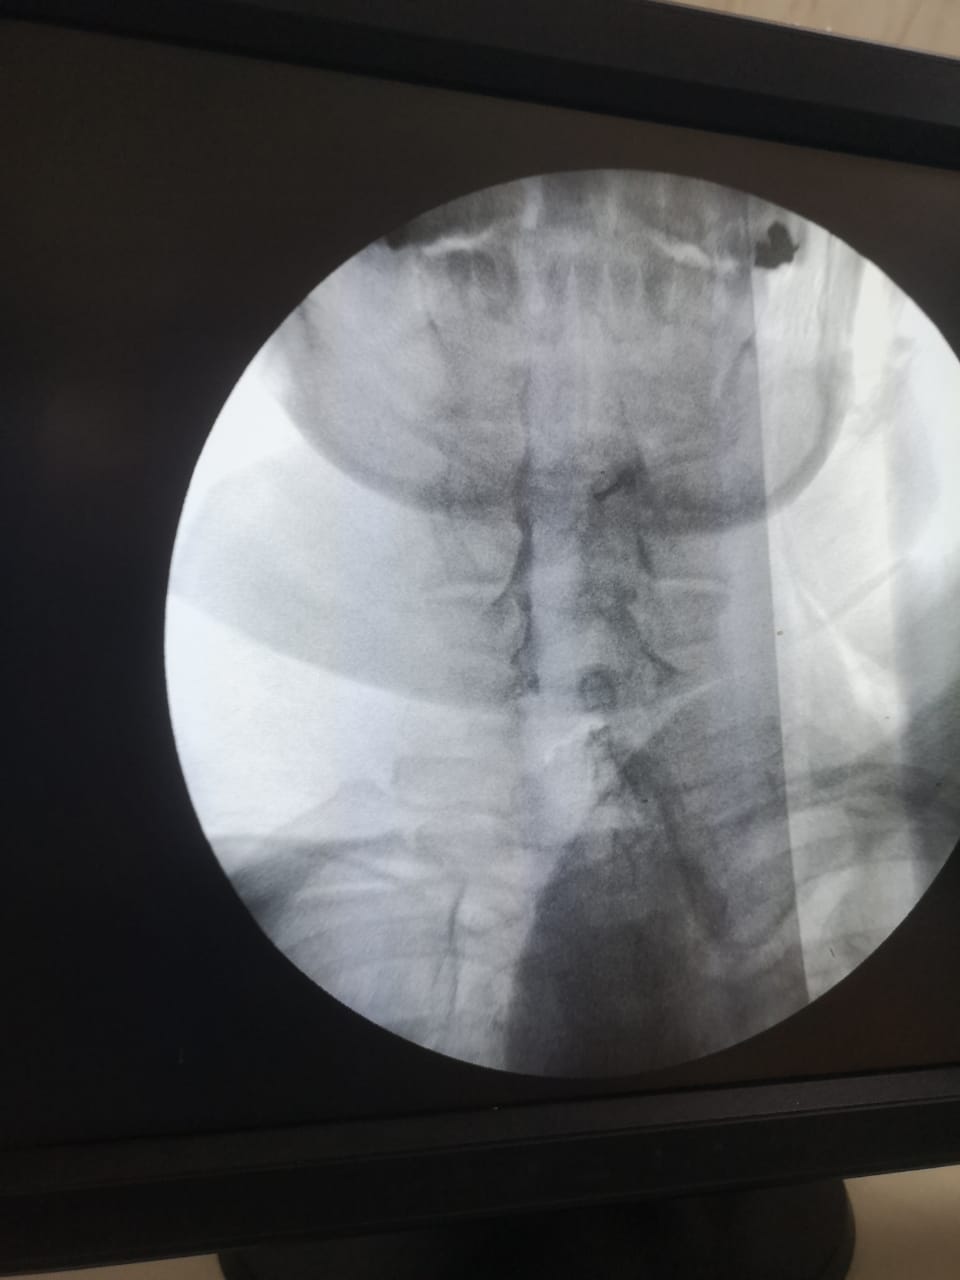

قام الفريق الطبي بوحدة علاج الألم بمستشفي الزقازيق العام، بقيادة الدكتور وائل أحمد الحبشاوي استشاري علاج الألم والتخدير، والدكتور يحيى الغندور أخصائي علاج الألم والتخدير، بعلاج حالتين وتقديم الخدمات الطبية لهما بالوحدة، بدون أي تدخل جراحي، حيث تم استقبال السيدة الأولي والتي تبلغ من العمر ٥٨ عام، وكانت تعاني من آلام بالرقبة وخدر وتنميل بالطرف العلوي الأيسر، وآلام أسفل الظهر وعرق النسا بالساق اليمنى، والتهاب بمفاصل العمود الفقري، بسبب غضاريف معتلة متعددة المستويات بالفقرات القطنية والعجزية، مع رفضها للتدخل الجراحي، وتم عمل حقن فوق الأم الجافية لجذور الأعصاب والقناة العصبية بالرقبة والفقرات القطنية والعجزية بمواد مضادة للإلتهاب، وتم عمل تسليك للقناة العصبية بمواد مذيبة للإلتصاقات، كما تم حقن مفصل الحوض الحرقفي المعتل، وعمل تردد حراري نابض على جذور الأعصاب، وعمل كي بالتردد الحراري على الأعصاب الناقلة للألم من المفاصل الخلفية للفقرات القطنية والعجزية، وتم خروج المريضة وتحسن الحالة بالمتابعة في العيادة، مع توجيهها لإجراء جلسات العلاج الطبيعي، وكانت الحالة الثانية مريض يبلغ من العمر ٥٥ عاما، يعاني من آلم أسفل الظهر وألم بالساقين نتيجة لضيق القناة العصبية بمنطقة الفقرات القطنية، وتم حقن القناة العصبية بمواد مذيبة للإلتصاقات مع مواد مضادة للإلتهابات، وتم خروج المريض بحالة جيدة بعد تقديم العلاج اللازم له، مع التوصيات الطبية بالمتابعة بعيادة علاج الألم.